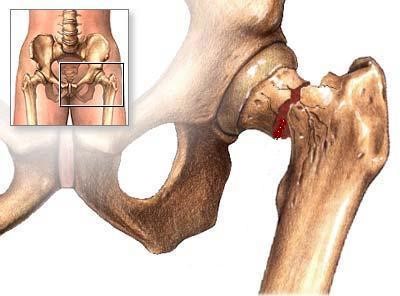

Het heupgewricht bestaat uit een heupkop (= onderdeel van het bovenbeen) en een heupkom (= onderdeel van het bekken). Wanneer er gesproken wordt over een ‘gebroken heup’, wordt er meestal bedoeld dat het bot vlak onder heupkop is gebroken (de ‘hals’ van de heup), of het bovenbeensbot vlak onder de hals. Een gebroken heup is vrijwel altijd het gevolg van een val, waarbij er op de aangedane zijde is gevallen. Een gebroken heup treedt meestal op bij ouderen vanwege zwakker wordend bot (osteoporose) en een verhoogde valneiging, maar kan ook bij jongeren voorkomen.

Operatie: in de meerderheid van de gevallen is er een indicatie voor operatie. Het doel van de operatie is de patiënt pijnvrij te krijgen en zo snel mogelijk weer uit bed te krijgen, aangezien patiënten snel zieker worden als ze alleen maar in bed kunnen blijven liggen (ontstaan van oa. longontstekingen en doorligplekken) Het soort operatie is afhankelijk van onder andere de leeftijd van de patiënt, de plaats van de breuk en de stand van de breuk. Als de breuk in de nek van de heup zit (vlak onder de kop), dan zal er gekozen worden voor het vastzetten van de heupkop met bijvoorbeeld 1 of meer stevige schroeven in de heupkop, of voor het vervangen van de heupkop met een heupprothese. Indien de breuk onder de nek en dus meer in het bovenbeen zit, zal er gekozen worden voor of een stevige schroef in een plaat, of voor een stevige schroef met een pen in het bovenbeensbot.